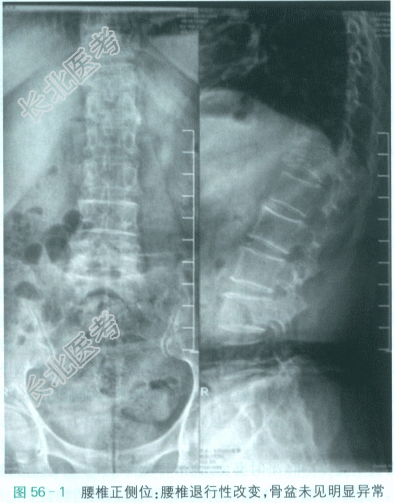

(5)腰椎X线片检查;腰椎退行性改变,骨盆未见明显异常(见图56-1)。